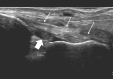

Ankle sonography is one of the most commonly ordered examinations in the field of osteoarticular imaging, and it requires intimate knowledge of the anatomic structures that make up the joint. For practical purposes, the examination can be divided into four compartments, which are analyzed in this pictorial essay: the anterior compartment, which includes the tibialis anterior, extensor hallucis longus, and extensor digitorum longus tendons; the accessory peroneus tertius tendon; and the extensor retinaculum; the medial compartment (tibialis posterior, flexor digitorum longus, and flexor hallucis longus tendons; the flexor retinaculum; the medial collateral-or deltoid-ligament, and the neurovascular bundle); the lateral compartment (peroneus longus, peroneus brevis, and peroneus quartus tendons; superior and inferior peroneal retinacula, lateral collateral ligament); and the posterior compartment (Achilles tendon, plantaris tendon, Kagar's triangle, superficial, and deep retrocalcaneal bursae). Scanning techniques are briefly described to ensure optimal visualization of the various anatomic structures.